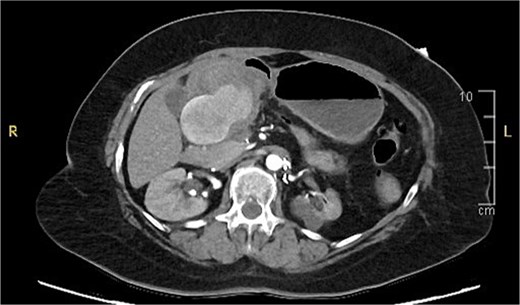

A computed tomography (CT) of the abdomen with IV portal venous contrast demonstrated proximal gastric dilatation due to a 7.6 cm gastric pyloric mass concerning for malignancy (Fig. 1). Other findings included small volume pancreatic parenchymal calcifications with no ductal dilatation. She was decompressed via nasogastric tube and planned for gastroscopy and feeding tube insertion. Gastroscopy demonstrated a partially obstructing extraluminal mass at the gastric antrum, able to be traversed to the second part of the duodenum (Fig. 2). A nasojejunal feeding tube was placed and the nasogastric tube was left in for decompression. An endoscopic ultrasound the following day demonstrated Doppler signal in the mass, confirmed to be a large 6.2 × 4.2 × 7.0 cm pseudoaneurysm arising from the GDA on a subsequent CT mesenteric angiogram (Fig. 3). Coil angioembolization of the pseudoaneurysm was successfully done via common femoral access (Fig. 4). She was commenced on NJ feeding and supplemental parenteral nutrition. She recovered well and was discharged on puree diet. Repeat imaging at 4 weeks demonstrated resolution of the pseudoaneurysm and returned to normal diet 6 weeks post presentation.

Contrast-enhanced CT of the abdomen. Axial view showing gastric outlet obstruction.